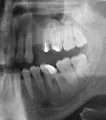

Волнуют мои зубы. Мне кажется, что мои зубы находятся в крайне запущенном состоянии. Как привести мои зубы в приемлемый вид? Мне кажется, что запломбированные зубы плохо выглядят. На верхней левой четверке выпала пломба.

Ваши зубы скорее всего требуют срочного лечения. Где-то возможно хроническое воспаление (периодонтит), а где-то и пульпит (воспаление нерва).